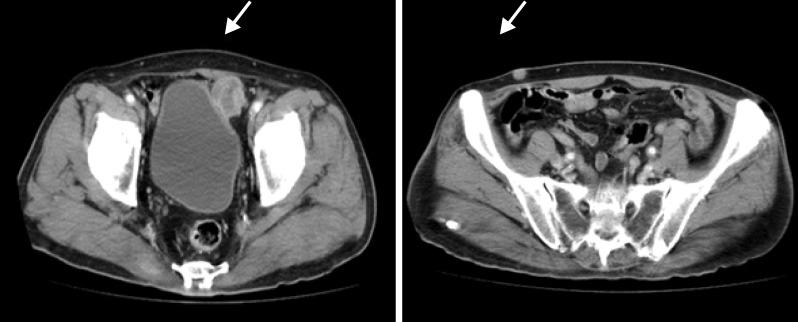

A 71-year-old man was referred for painless hematuria and a bladder tumor. Cystoscopy and computed tomography revealed a 3-cm oval nodular mass on the left lateral side of the bladder. The patient underwent a complete transurethral resection of the lesion and histology showed a proliferation of atypical spindle cells with inflammation consistent with a myofibroblastic tumor. After 4 and 7 months, follow-up cystoscopy demonstrated nodular mass lesions and transurethral resection of bladder tumor was done, which showed chronic cystitis and a recurred myofibroblastic tumor, respectively. Five months later, multiple lymph node, bone, and soft tissue metastases were found by positron emission tomography. The patient was treated first with palliative chemotherapy, including doxorubicin and cisplatin. After that, radiologic studies showed disease progression but the patient refused further treatment and died 6 months later.

一名71岁男性因无痛性血尿和膀胱肿瘤前来就诊。膀胱镜检查和计算机断层扫描显示膀胱左侧有一个3厘米的椭圆形结节状肿块。患者接受了病变的完全经尿道切除术,组织学检查显示非典型梭形细胞增生并伴有炎症,符合肌成纤维细胞瘤。4个月和7个月后,随访膀胱镜检查发现结节状肿块病变,分别进行了膀胱肿瘤经尿道切除术,结果显示为慢性膀胱炎和复发性肌成纤维细胞瘤。5个月后,正电子发射断层扫描发现多处淋巴结、骨骼和软组织转移。患者首先接受了姑息化疗,包括阿霉素和顺铂。此后,影像学研究显示疾病进展,但患者拒绝进一步治疗,6个月后死亡。